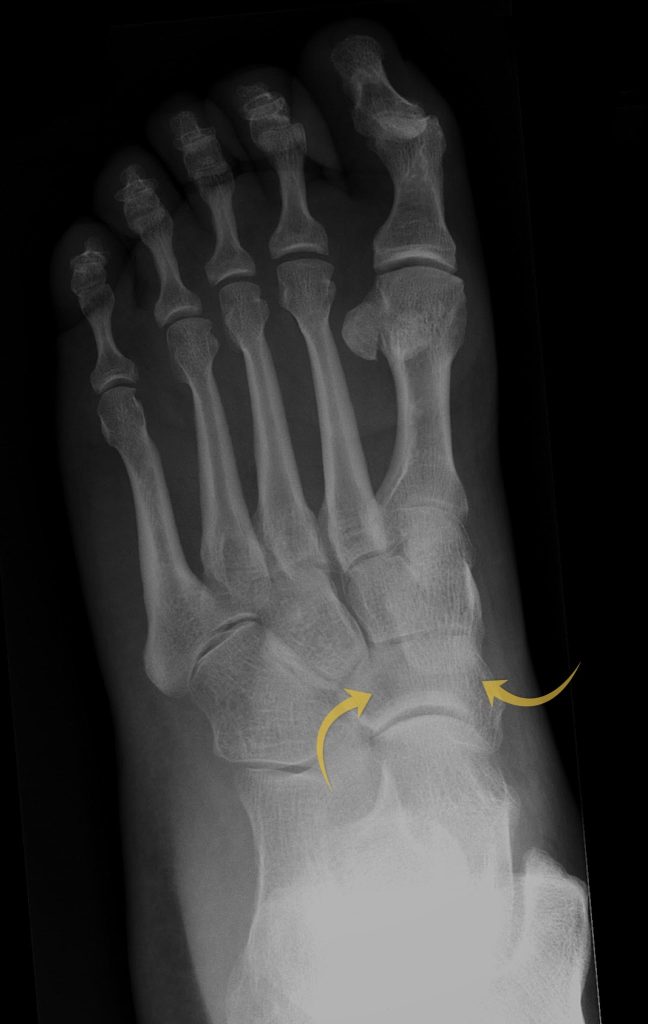

Case 10

For the last case let’s look at a foot X-Ray. What are the arrows pointing at?

Choose from one of the following options: